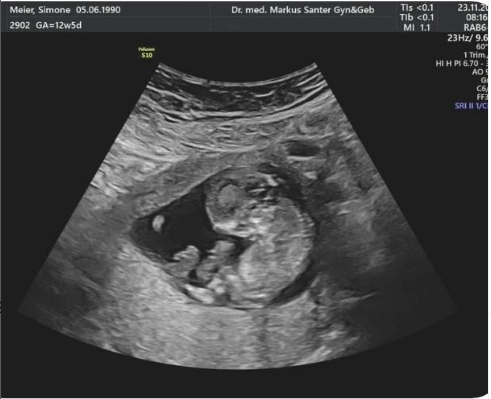

Das ist unsere Geschichte: in der 13. SSW gingen wir zum Gynäkologen für einen Untersuch inkl. Nackenfaltenmessung etc. Ich war bei dieser Schwangerschaft sehr angespannt und nervös auf das Resultat – was sich später leider bestätigte.

Beim Ultraschall war nichts auffälliges zu sehen, jedoch waren beim Bluttest die Risikowerte für eine Trisomie erhöht, was dazu führte, dass wir zusätzlich ein grosses Blutbild für eine genaue Diagnose machten.